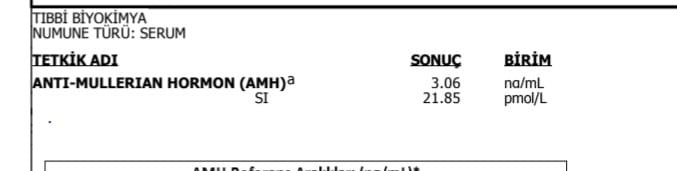

Hormon ve vitamin değerleri ilk tüp bebek merkezine ait.

Hormon ve vitamin değerleri ilk tüp bebek merkezine ait.